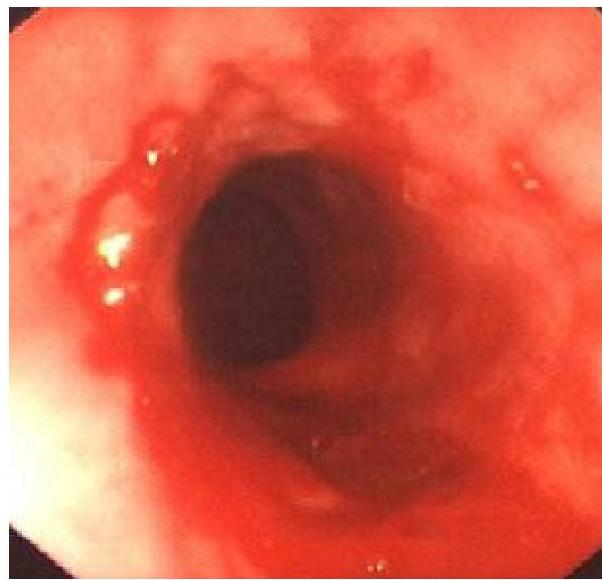

- Endoscopy (with biopsy): To look for erosions or ulcer of esophagus

- Endoscopic appearance

- Histological findings

Diagnostic criteria — The diagnosis of EoE requires all of the following:

- Eosinophil-predominant inflammation on esophageal biopsy